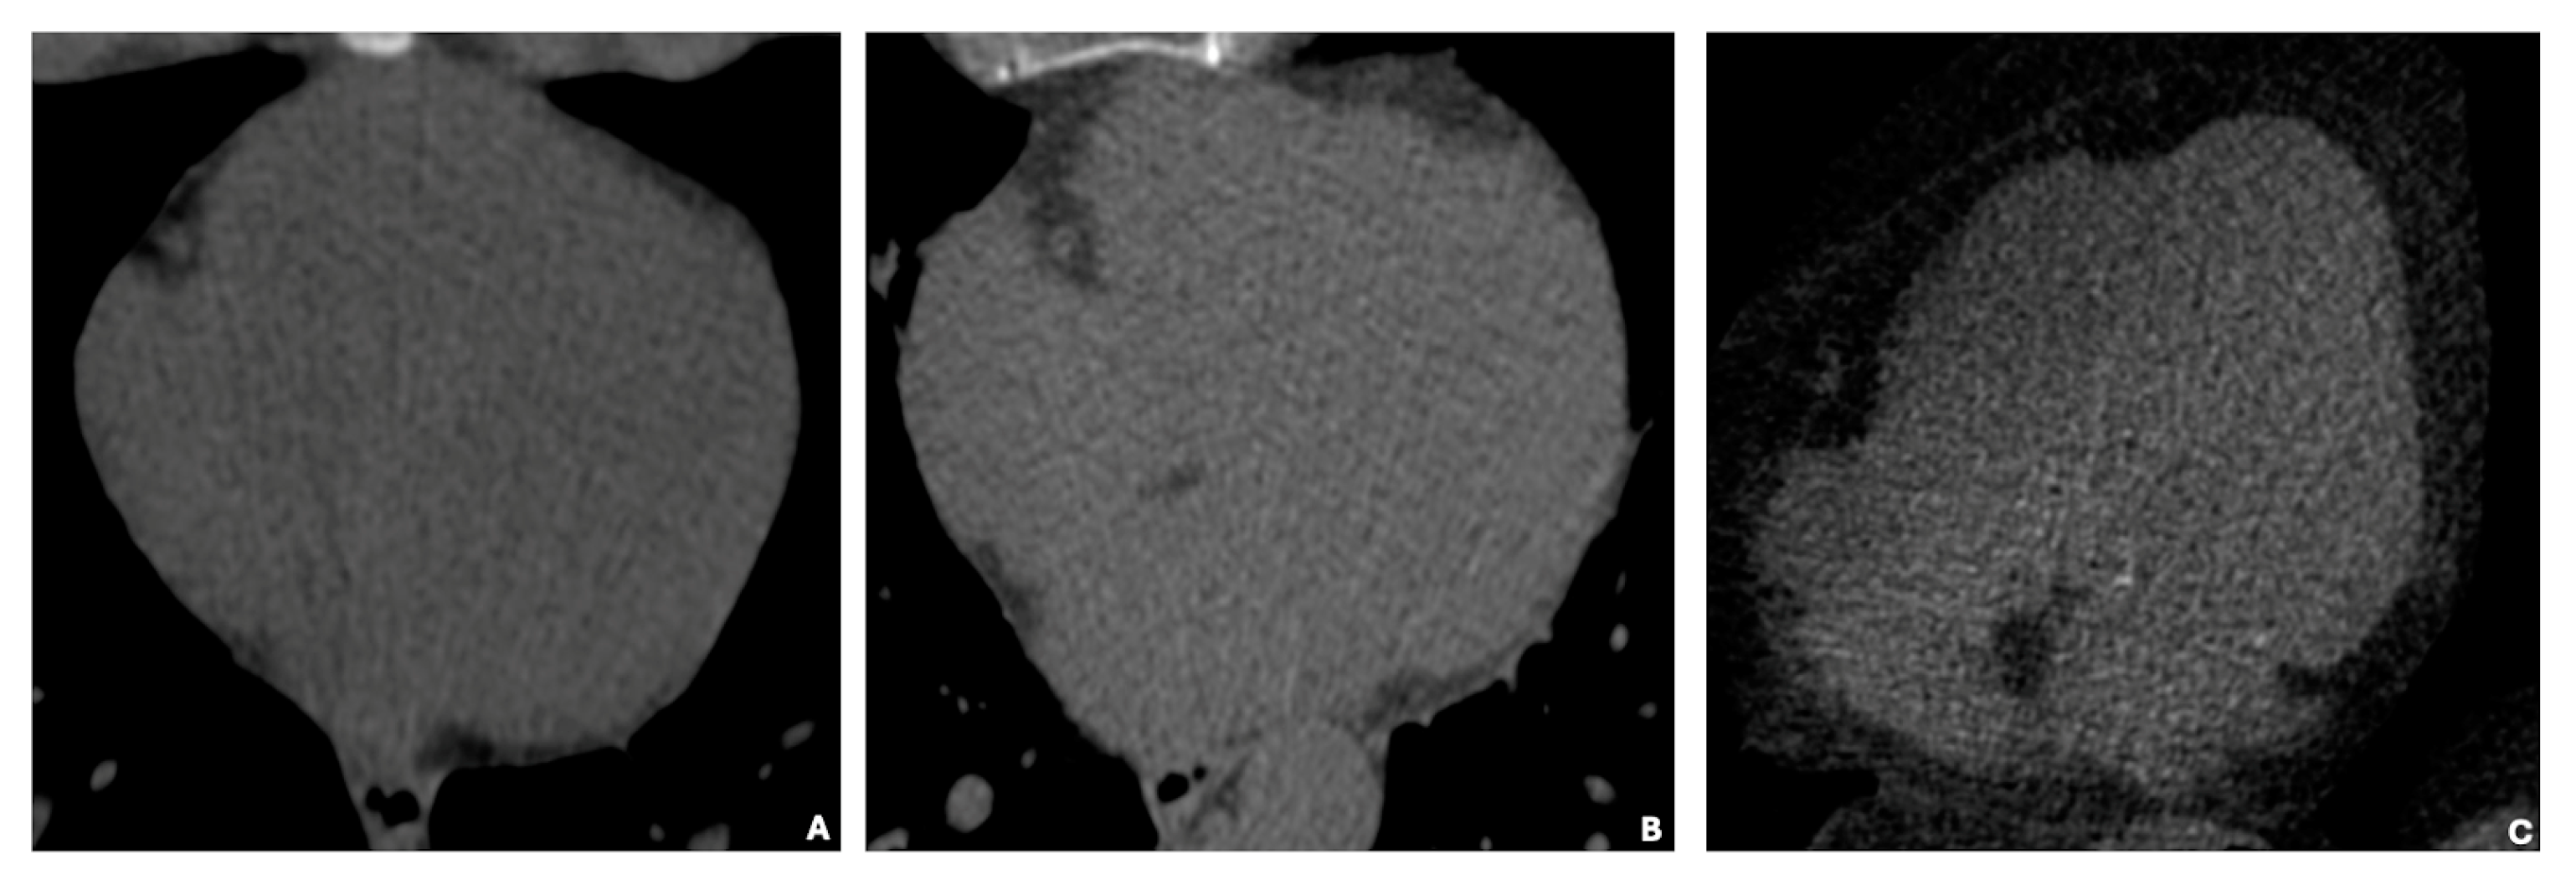

In Figure 3, basal cardiac axial scans obtained through non-contrast computed tomography (NCCT) illustrate three distinct categories of EAT volume: low (35 cm3), average (125 cm3), and high (414 cm3). The images visually depict the increasing EAT volume across these categories.

Figure 3. (AC) show basal cardiac axial scans obtained through non-contrast computed tomography (NCCT) of individuals with varying epicardial adipose tissue (EAT) volumes. The images represent three distinct categories: low EAT volume (35 cm3) (A), average EAT volume (125 cm3) (B), and high EAT volume (414 cm3) (C).